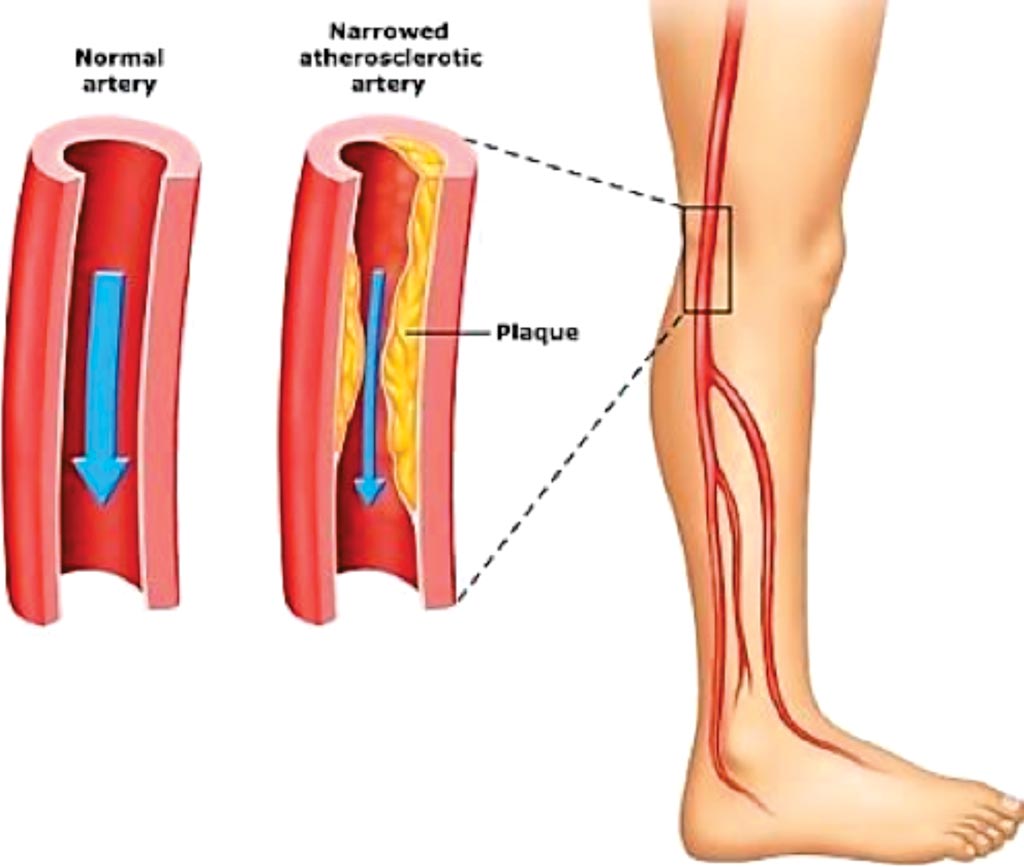

Изображения, связанные с атеросклерозом нижних конечностей и его лечением